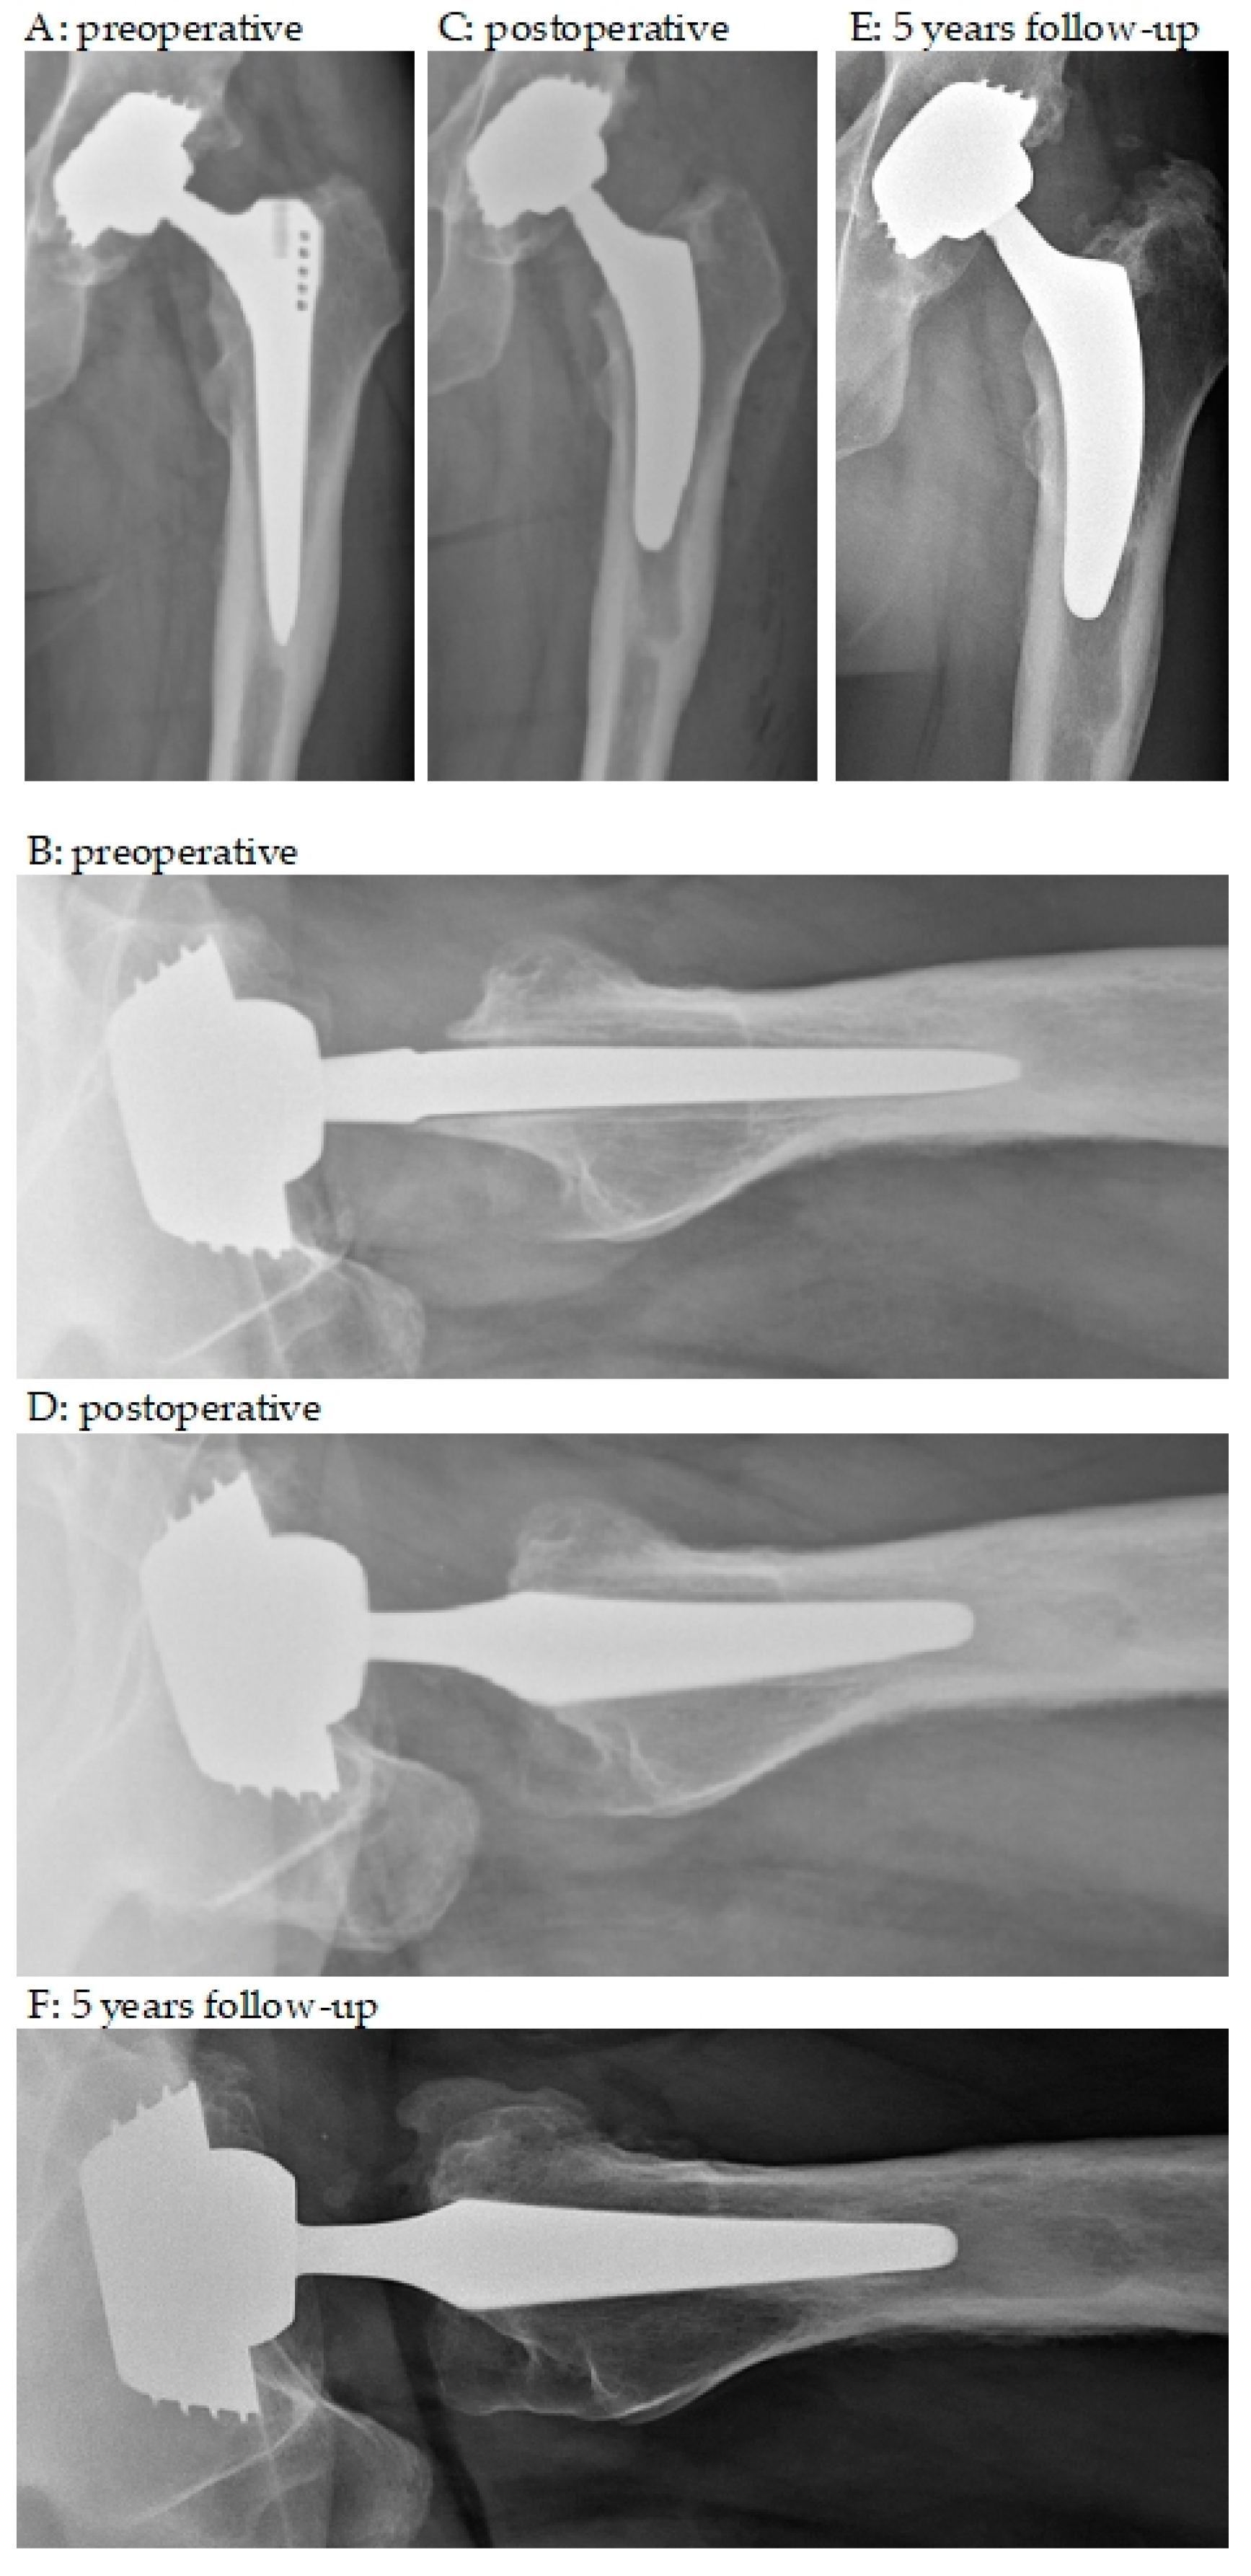

3.2. Radiographic Outcomes